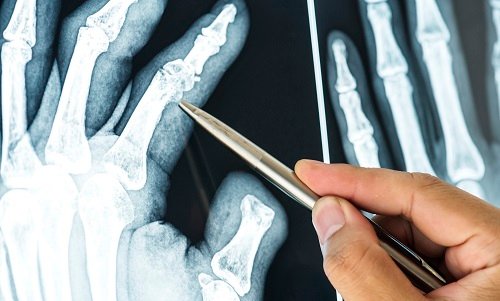

Dr. M.S. Narula is a leading trauma orthopaedic surgeon who offers minimally invasive and small incision techniques to provide state of the art care to his patients. Whether you require a second opinion or emergency treatment, he offers specialized fracture management for simple, complex and neglected fracture.

Orthopedic trauma cases are particularly difficult to treat, but with the right skill, technique, and experience, Dr. M.S. Narula provides excellent care to treat the trauma and progress towards complete recovery & minimal or no disability.